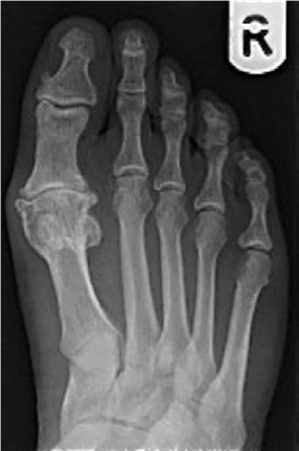

Foot and ankle structured oral questions3: The rheumatoid foot EXAMINER : Please have a look at this radiogra…